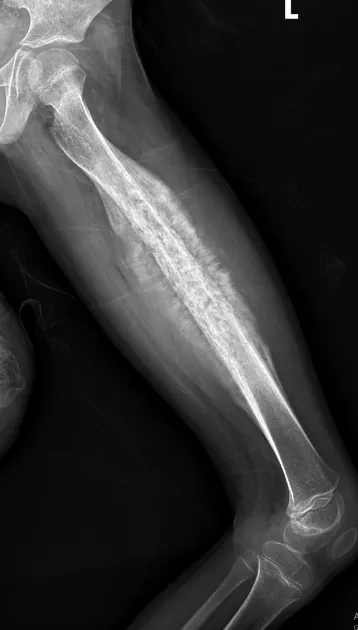

Ewing Sarcoma: Key Features - Diaphyseal Danger Zone

- Small round blue cell tumor; neuroectodermal origin. 2nd common, children.

- Site: Diaphysis (long bones, pelvis).

- X-ray: Lytic, "onion-peel", "moth-eaten".